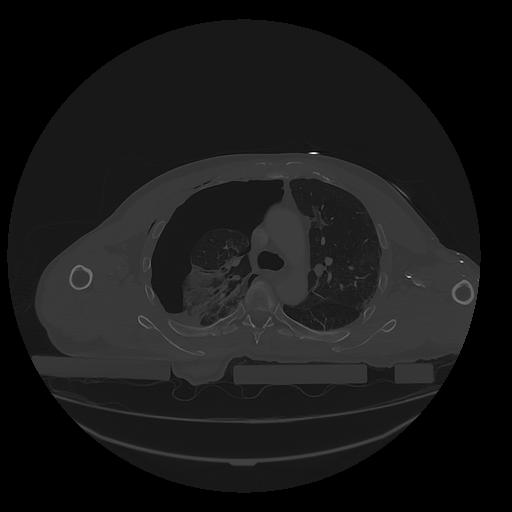

31 PULMON,CE,Vol,1.0,PULMON,,